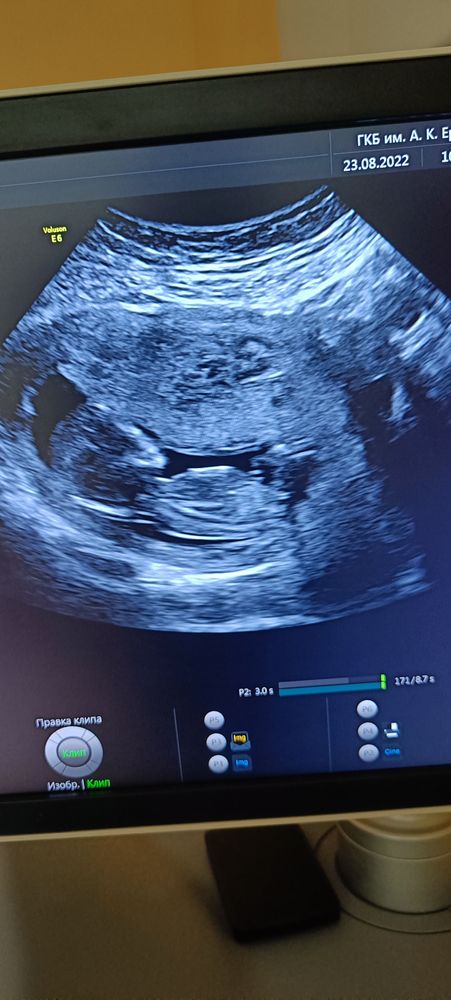

Лисица в Благополучная беременность 3 года Гадание на пол по УЗИ 13,3 недели УЗИ, КТГ, доплер Вот и первый скрининг! Что видно? Погадаем? Посмотрите еще 20 записей на эту тему Отменить Ответить Алина Девчуля, точно) 27.08.2022 Ответить Сентябринхен Я бы тоже сказала девочка! 23.08.2022 Ответить Маргарита Девочка❤️ 23.08.2022 Ответить Евгения Девочка 23.08.2022 Ответить Ксения Пискарева У знакомой похожее узи, у неё мальчик)) я за мальчика)) 23.08.2022 Ответить Леди баг Девочка 23.08.2022 Ответить Леди баг Если это бугорок половой, то по его наклону-девочка. 23.08.2022 Ответить УЗИ на 36 неделе Не разбираюсь в этом, врач молчит Чаты Беременных Выберите чат: Январята-2026 Февралята-2026 Мартята-2026 Апрелята-2026 Майчата-2026 Июнята-2026 Июлята-2026 Августята-2026